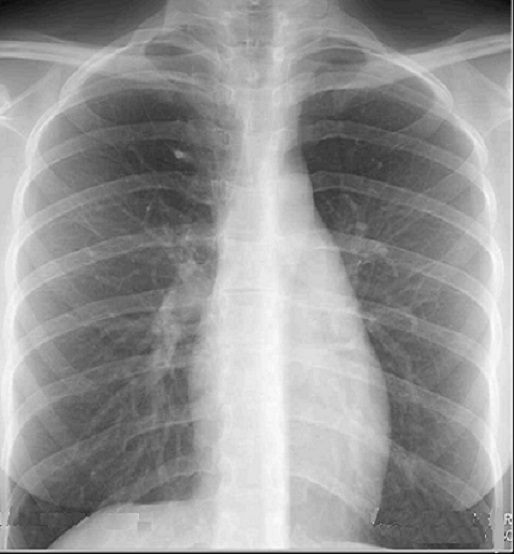

Image radiologique normale

de petit scissure ascessoire Azygos du lobe superieure

droit . Cliche standarnise PA de face du poumon |

Même cas en coupe TDM

coronal , fenetre mediastinale . La plie muqueuse de la

plevre de veine Azygos être en vue très nette à droit

|